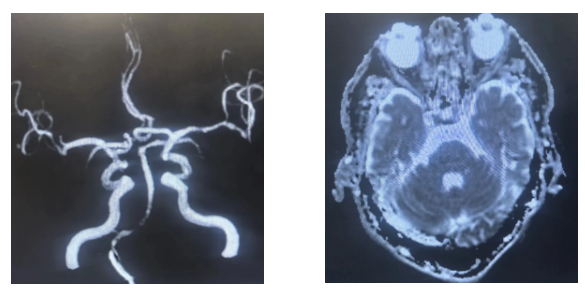

为明确诊断并制定治疗方案,神经内科与介入科医生团队迅速开展联合会诊,一致认为介入治疗是首选方案。随后,由独建库主任在DSA(数字减影血管造影)引导下,成功为患者实施了介入手术。

CTADSA(血管造影):可清晰显示血管狭窄的位置和程度,是诊断的金标准。

介入治疗

目前临床上常用的微创方法。医生通过股动脉穿刺,将球囊或支架送至狭窄处,扩张并支撑血管,恢复血流通畅。该方法创伤小、恢复相对较快。